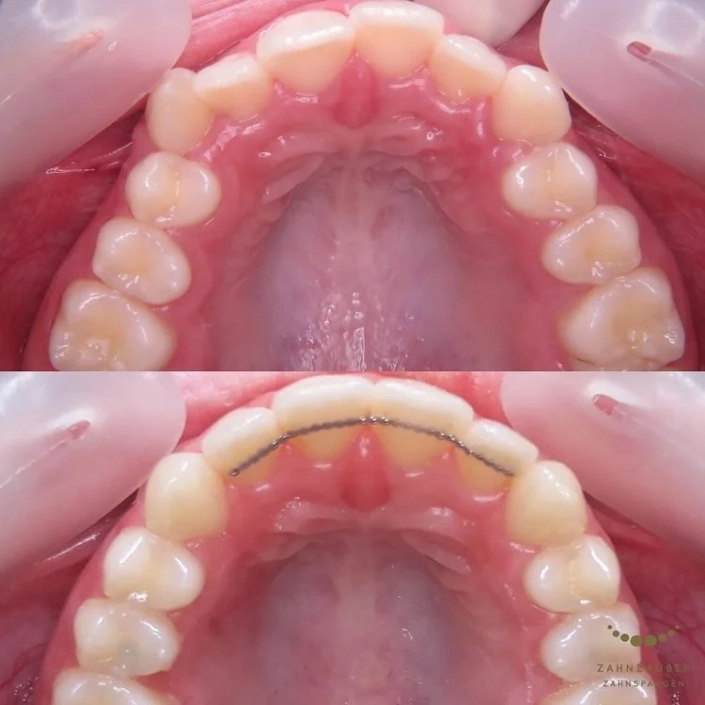

Vorher: Der Patient kam mit einer asymmetrischen Klasse-II-Malokklusion, einem Engstand und einem Vorbiss von 14 mm. Zusätzlich lag eine retrognathe Mandibula vor, was die Kieferstellung beeinträchtigte und funktionelle Probleme verursachte.

Nachher: Nach der zweijährigen Behandlung, in der vier Zähne entfernt und der Unterkiefer operativ korrigiert wurden, wurde ein dauerhafter Retainer eingesetzt, um die ideale Position der Zähne langfristig zu stabilisieren. Der Patient verließ die Praxis mit einem harmonisch ausgerichteten und funktional verbesserten Gebiss.